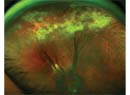

A Complicated, Recurrent RRD

How adding a scleral buckle corrected a complex proliferative vitreoretinopathy-related recurrent retinal detachment.